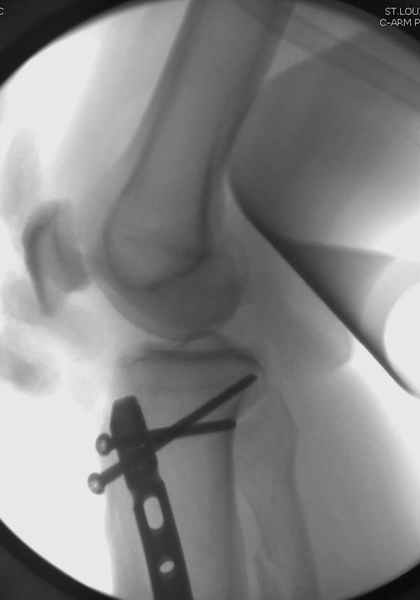

У меня молодой врач на линии, снимки отправил через эл. почту,

спрашивает что делать с больным который поступил недавно, фермер 55 лет падение при пьяной драке в баре, года два назад перенес операцию на лодыжке, на снимках и КТ перелом без вовлечения сустава,

Здесь мы использовали новый Synthes Nail с дополнительными дырками, в проксимальной части 4: по две косых и поперечные (один стандартный а другой динамический), в дистальной части две поперечные, прямая и косая. Вес больного более 120 кг, нагрузку начнем через месяц.

Получилось красиво, поздравляю. Вверху можно было ограничиться одним винтом во фронтальное статическое отверстие, зачем два 45-градусных?

При такий спирали задний край tibia может быть сломан - нет ли этого в данном случае? На всякий случай можно было ввести 1-2 винта 4,5 мм спереди назад мимо гвоздя. Хотя самый дистальный блокирующий винт, возможно, зацепил этот отломок. А какой тут диаметр гвоздя и locking винтов?